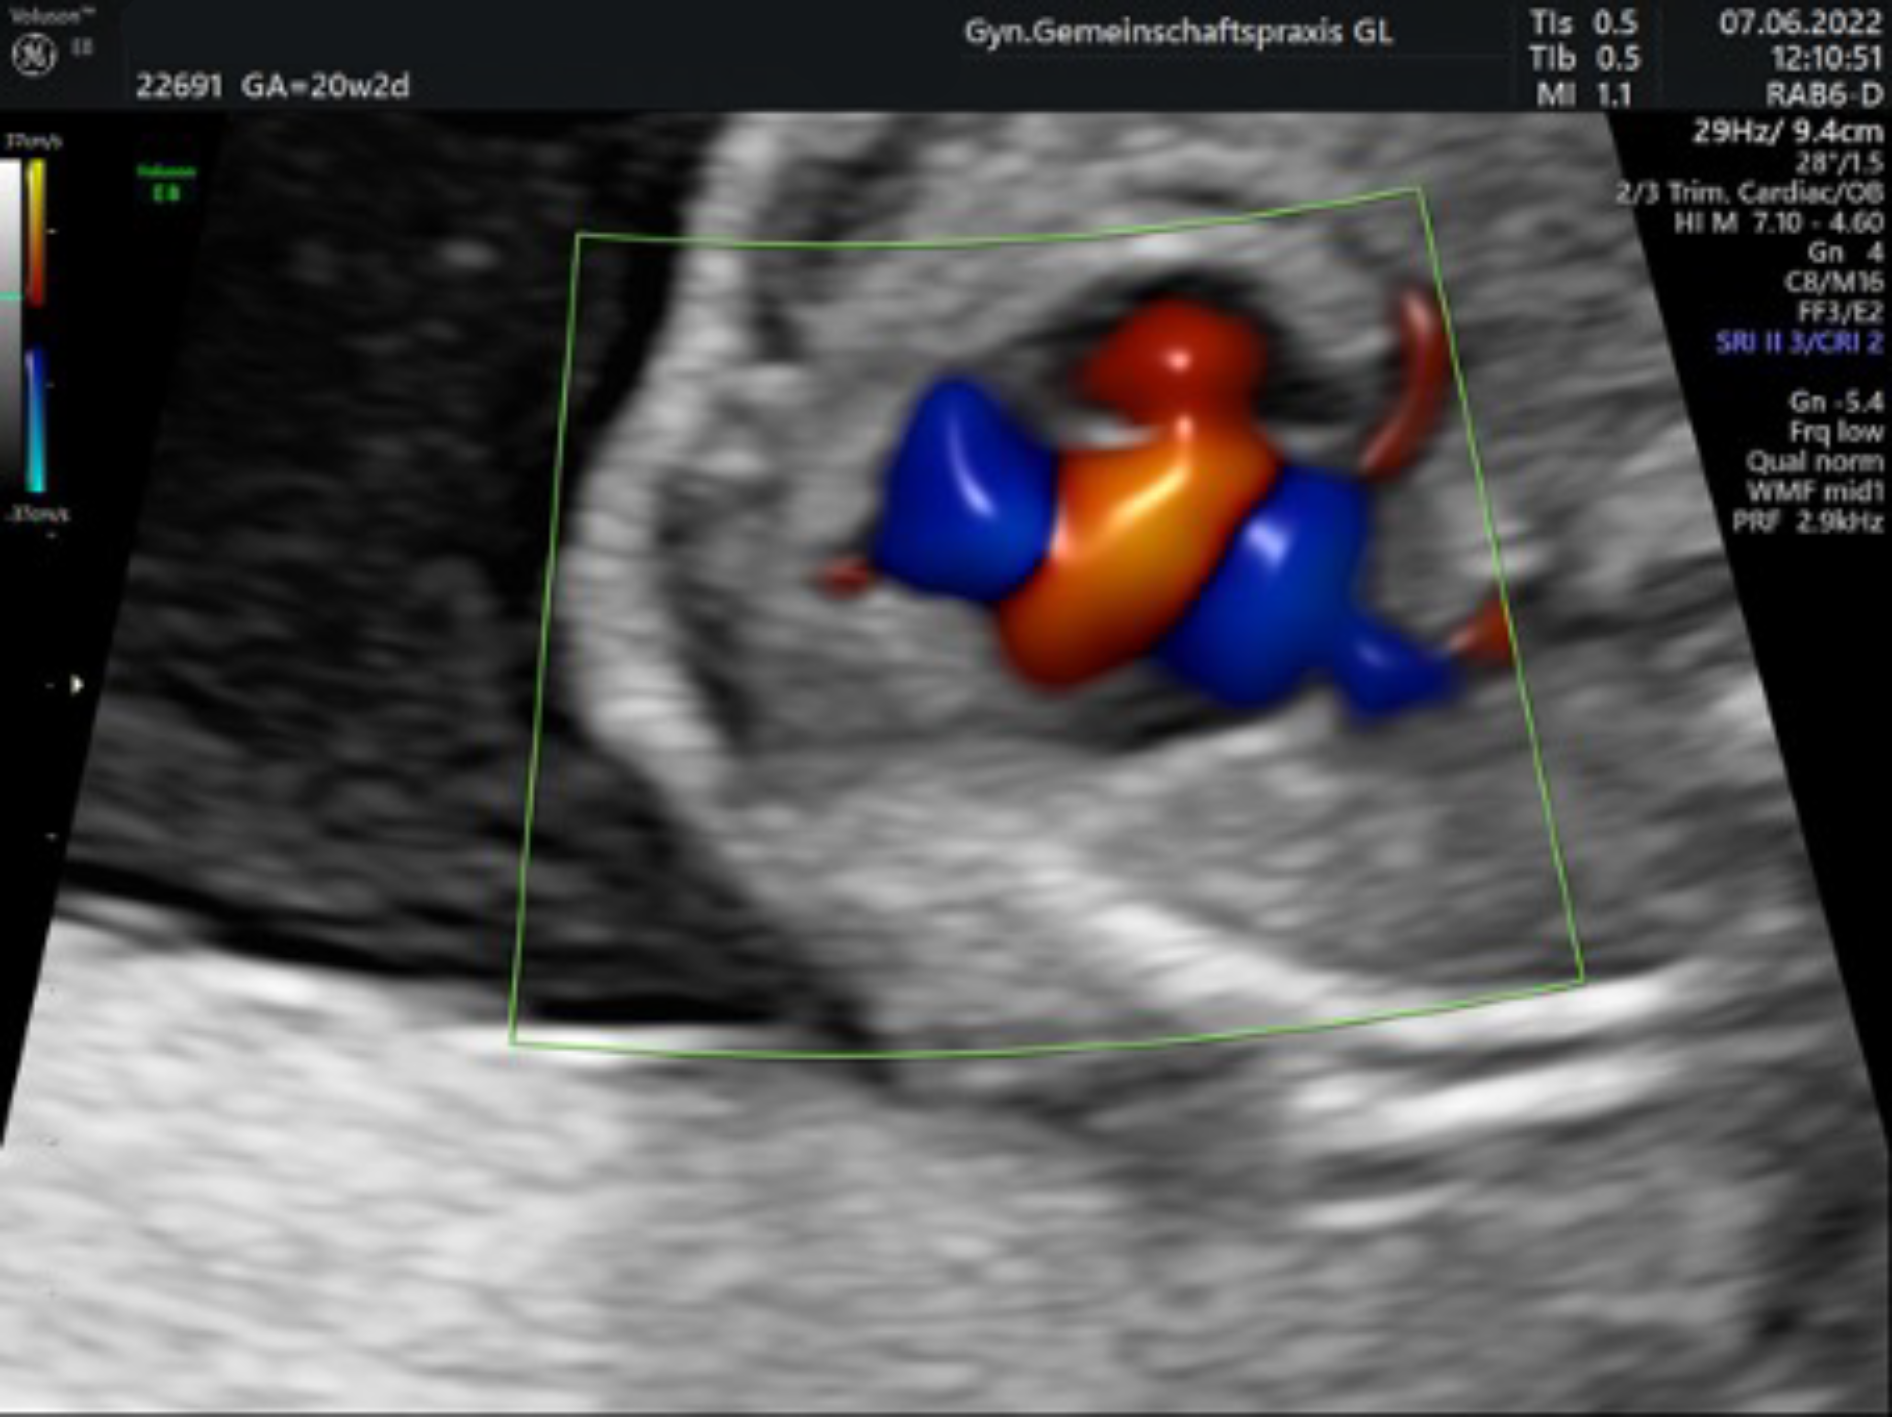

Ultraschall in der 20. – 22. Schwangerschaftswoche mit Organfehlbildungsdiagnostik und Untersuchung der Blutversorgung nach den Richtlinien der DEGUM Stufe II

Mit einem hochauflösenden Ultraschallgerät werden dabei alle Organsysteme des Kindes gründlich untersucht um nach Hinweisen auf Fehlentwicklungen zu suchen. Besonderes Augenmerk liegt dabei auf dem Herzen, dessen richtiger Aufbau und Funktion mithilfe farbcodierter Blutflussmessungen (Doppleruntersuchung) überprüft wird.

Auch die Versorgung des Kindes durch die Mutter kann gemessen werden. Hierbei können sich auch frühe Hinweise auf eine spätere sogenannte „Schwangerschaftsvergiftung“ der Mutter finden.